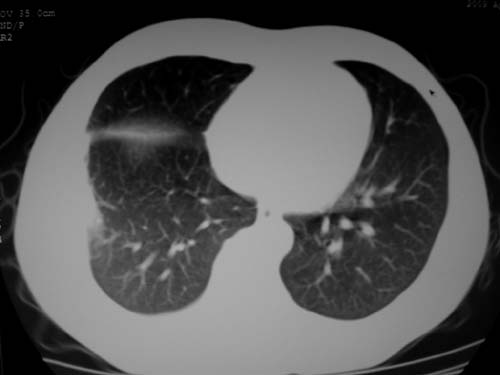

标题: CT19540: 31岁。自述结核性胸水治疗两个月后,在外院拍x线发 [打印本页]

标题: CT19540: 31岁。自述结核性胸水治疗两个月后,在外院拍x线发

病灶也是发生于结核球好发部位,支持结核

考虑结核性结节

考虑结核性胸膜炎,胸膜肥厚,不除外胸膜间皮瘤可能,建议复查。

支持结核,胸膜间皮瘤不排除.

结核性脓胸、肺内结核?